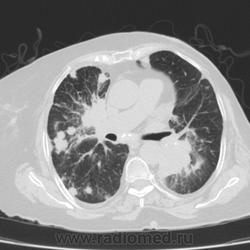

Метастатическое поражение легких.

Пожилая женщина, 76 лет находится на стац.лечении, провели СКТ дообследование.  Сопут- сr левой молочной железы. Такие множественные

поражения  в легких встречаются не часто.

Раннее несколько лет назад оперирована по поводу рака левой молочной железы.

Ну да, неспокойная работа, один тяжелее и  интересней другого. На обзорной рентгенограмме было всё видно прекрасно. Но терапевты направили, а я и не отказалась, чтобы в следующий раз знать- какие они бывают вторичные поражения легких.